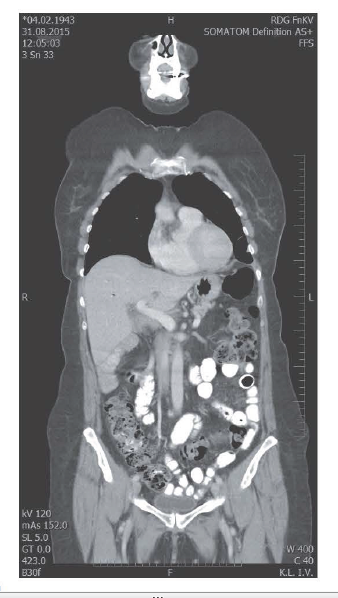

Poslední restaging

8/2015 bez známek diseminace či recidivy v oblasti odstraněných metastáz, pacientka ve výborném klinickém stavu bez neurologických či kognitivních poruch, bez dýchacích obtíží, zažívání prakticky bez komplikací ECOG 0-1